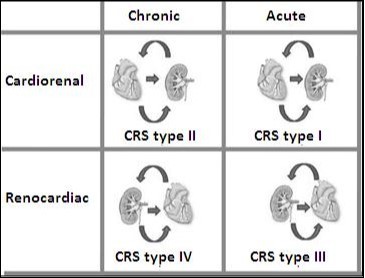

Renal blood flow is reduced, and/or the reduced venous return can result in renal congestion38, 39, 40) with secondary increase in renal interstitial pressure41. HFpEF and HFrEF are strongly associated with renal dysfunction39, 42). This finding endorses the definition of Cardiorenal syndrome. Figure 4.

Figure 4.Types of Cardiorenal syndrome. Note that this classification stages depend on if it is acute failure or chronic heart and if the insult is initially cardiac or renal.

This is the picture of the cardiorenal syndrome with high risk of death and rehospitalization. This syndrome has been classified by the Working Group of the initiative for the quality of dialysis, which proposes a 5 subtypes classification scheme academic way. This classification of 5 items is based on: a) if the principal organ of the dysfunction is the heart, kidney, or a third independent process that affects both the bodies and b) the acute or chronic nature of the disease. Table 1 summarizes the current 5 types of CRS.